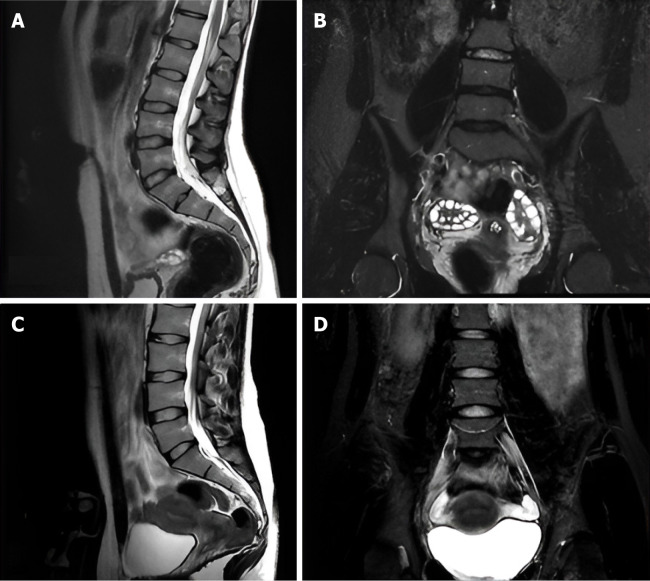

Background: Back pain and sciatica are common complaints that often require imaging for accurate diagnosis and management. Conventional lumbar magnetic resonance imaging (MRI) protocols typically include sagittal and axial T1 and T2 sequences; however, these may miss certain pathologies. The addition of coronal short tau inversion recovery (STIR) sequences offers the potential to enhance the detection of both spinal and extra-spinal abnormalities, thereby improving clinical decision-making and patient outcomes.

Aim: To evaluate the impact of adding coronal STIR sequences to routine lumbar MRI in diagnosing back pain and sciatica.

Methods: We prospectively analyzed data from patients aged 6 and older presenting with back pain or sciatica who underwent lumbar spine MRI at our institution. The standardized MRI protocol utilized included sagittal and axial T1 and T2 sequences, complemented by a coronal STIR sequence. Data on structural abnormalities were collected, reviewed, and analyzed using counts, percentages, and Fisher's exact test for categorical variables.

Results: Our cohort comprised 274 patients (115 males, 159 females; mean age 44.91 years). Notably, 39 patients exhibited abnormalities across all sequences, while 72.63% showed normal findings on the coronal STIR sequence. Importantly, 30.29% of cases were diagnosed as normal without the coronal STIR, and 36 patients with normal T1 and T2 sequences presented abnormalities on the coronal STIR. The coronal STIR sequence successfully identified 26 spinal and 10 non-spinal pathologies, including 17 cases of sacroiliitis, with a significant association (P < 0.0001) between sacroiliitis diagnosis and abnormalities visible solely on this sequence.

Conclusion: Integrating coronal STIR into routine lumbar MRI enhances detection of hidden spinal and extra-spinal pathologies, improves patient management, and offers a cost-effective, practical upgrade with significant diagnostic and clinical value.